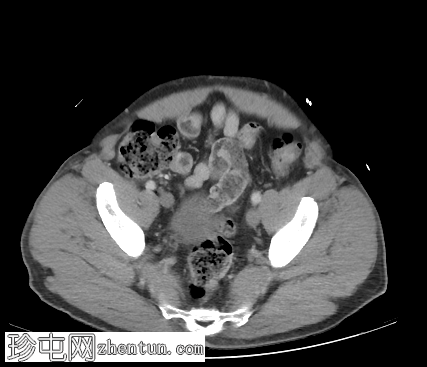

轴向C+门静脉期

右侧腹股沟斜疝,包含网膜脂肪,延伸至阴囊颈。疝囊内包含正常阑尾(轴向、冠状),符合Amyand疝。

双侧精索脂肪增多症。